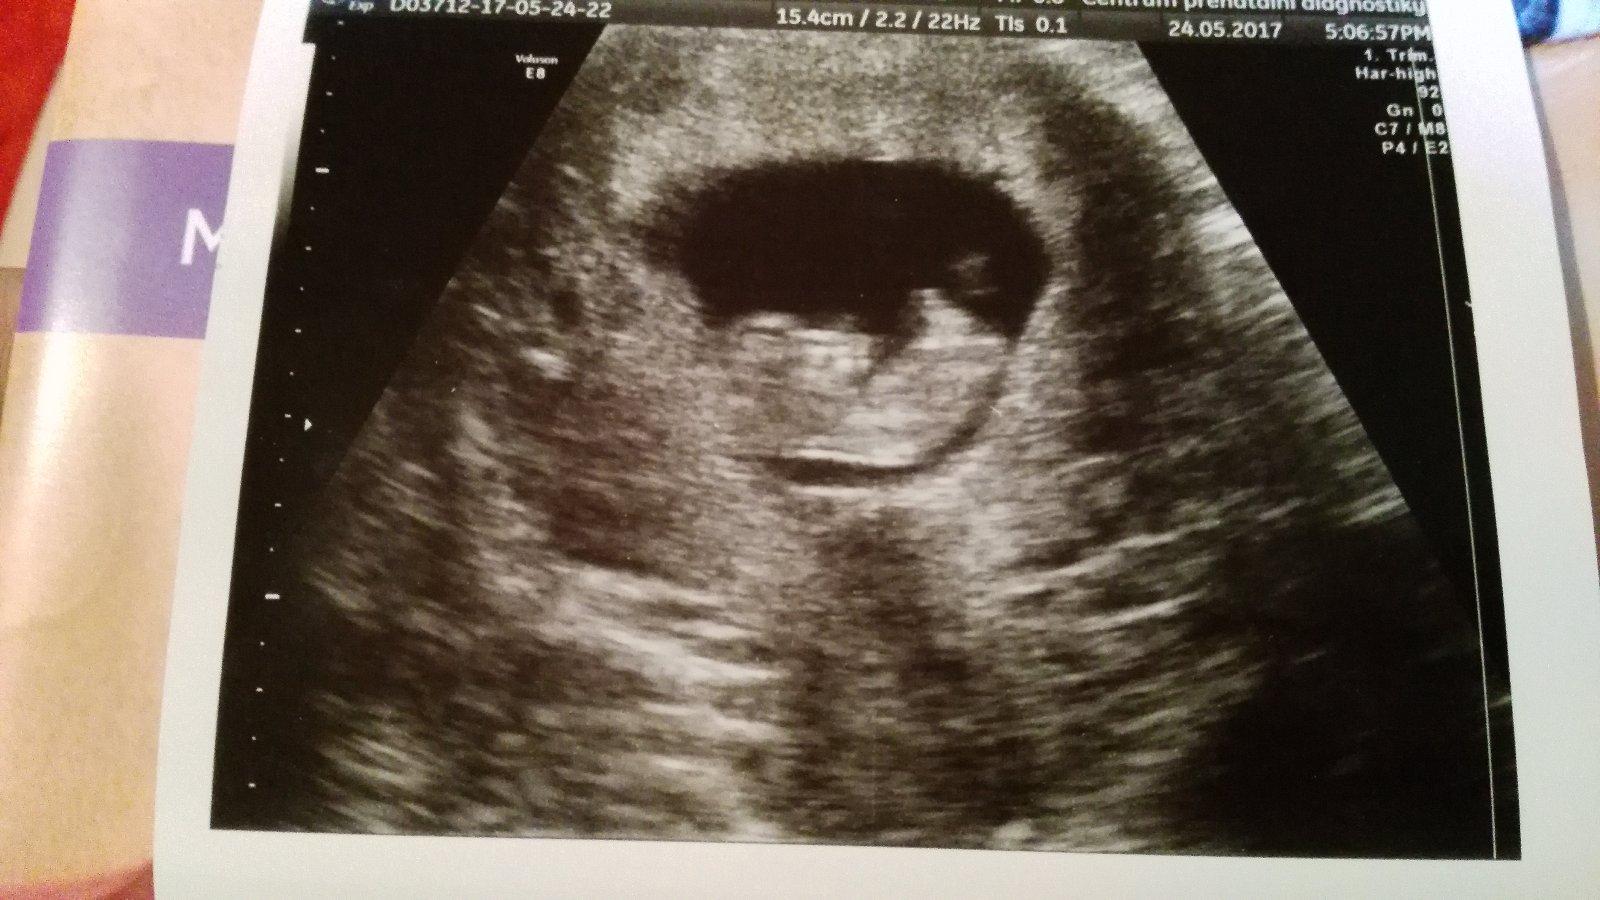

Tak rande s miminkem dopadlo super.Uz se srovnalo a odpovida presne podle MS dnes tedy 10+3. Krasne hopsalo,propinalo se v zadickach a mavalo rucickama a nozickama😍